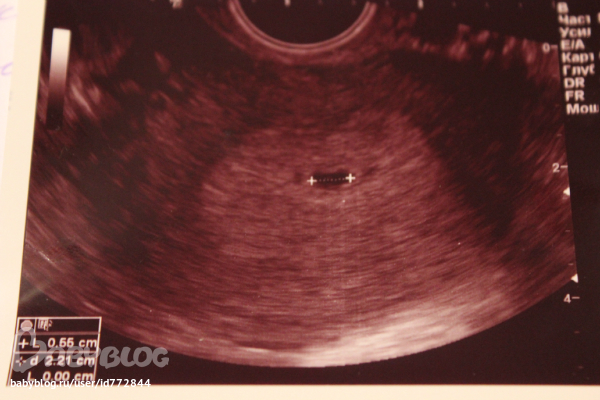

Мой уже по-старше(11 мм) будет внутри даже эмбриончик просматривался)))Ну всё равно, такая прелесть!!!!

Нам уже 5 недель и диаметр наш примерно 4 мм. Расположение низкое, чем я очень обеспокоена. Стараюсь не нервничать...

Казалось бы ну что тут видно?!А смотришь-КРАСОТА!!!!Такие приятные эмоции!!Самое лучшее фото в мире!!!Желаю вам крепкого здоровья!!!Растите большими и здоровенькими!!